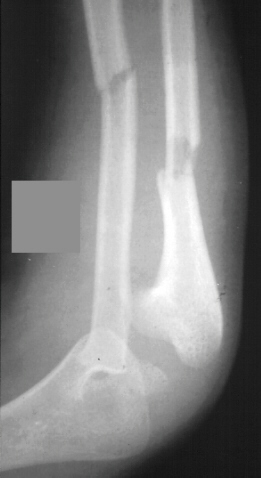

A 4 year and 6 month old male sustained a fall onto an outstretched left arm. He presented to the emergency room with forearm deformity and acute pain(image 1). It was treated with closed reduction and casting (image 2&3). The patient was brought back for another evaluation 10 months after the initial injury(image 4). An x-ray at that time was repeated. On physical examination, he has a prominence over the left radial head. There is full flexion and extension. He has full pronation but lacks 30 degrees of full supination. He is neurovascularly intact(image 5).